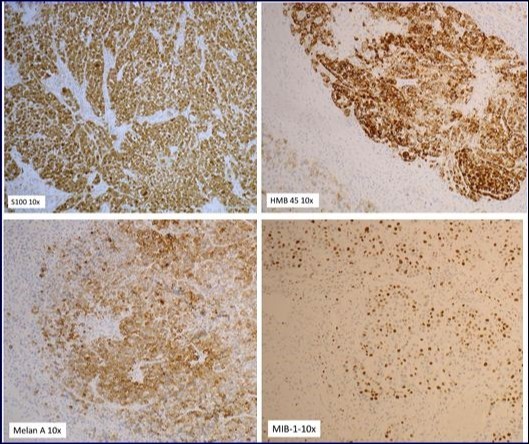

Immunohistochemically, cells were diffusely positive for S100 protein and focally for HMB45 and Melan A. They were negative for MNF116, desmin, smooth muscle actin (SMA) and CD45. The mitotic proliferation index estimated by the Mitotin index (MIB) was 60 to 70%. Three periparotidal lymph nodes were without injury. Skin result was normal (Figure 3).

Figure 3.The immunohistochemistry for both S100 and HMB 45 were positive establishing diagnosis of primary malignant melanoma of the parotid.

Histologically, tumor cells are large, mostly non-cohesive with abundant eosinophilic cytoplasm, a marked pleomorphic nucleus and prominent nucleoli. The core is compsed of enlarged nucleoli and often pushes the periphery. Immunohistochemically, cells are diffusely positive for S100 protein and HMB45. Melan A is positive in 80% and MiTF in the 90% of melanoma 11.